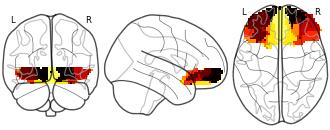

Connectivity-Based Parcellation of the Human Orbitofrontal Cortex: K=3...

EmailClick to copy linkLink copied Cite(2024). Connectivity-Based Parcellation of the Human Orbitofrontal Cortex: K=3 cluster map [Dataset]. http://identifiers.org/neurovault.image:887624niftiAvailable download formatsUnique identifierhttps://identifiers.org/neurovault.image:887624Dataset updatedNov 18, 2024License

Cite(2024). Connectivity-Based Parcellation of the Human Orbitofrontal Cortex: K=3 cluster map [Dataset]. http://identifiers.org/neurovault.image:887624niftiAvailable download formatsUnique identifierhttps://identifiers.org/neurovault.image:887624Dataset updatedNov 18, 2024LicenseCC0 1.0 Universal Public Domain Dedicationhttps://creativecommons.org/publicdomain/zero/1.0/

License information was derived automaticallyDescriptionK=3 cluster map based on N=13 participants.

Collection description

K-means cluster maps of orbitofrontal cortex with K=2, 3, 4, 5, 6, and 7 clusters based on resting-state fMRI data.